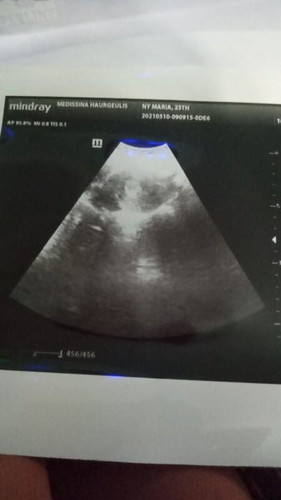

Pengalaman make tespek pas belum telat haid dapet garis 2 tp yg satunya samar bngt, pas deket jadwal haid garis 2 satu samar lumayan, pas telat haid 2 hari tespek hasilnya 2 garis tegas , alhamdulillah☺️ Pernah ngalamin keguguran jd seprotektif ini🤭 Seminggu kemudian priksa ke dokter kandungan pas di USG udah keliatan kantong kehamilan😍 Balik USG lg bulan depan bismillah semoga sehat kuat perkembangan babynya bagus😇 Aamiin🤲#1stimemom